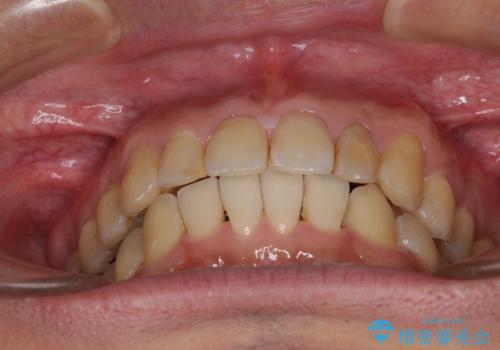

前歯のデコボコと下顎の八重歯 インビザラインによる矯正治療

- 前歯のデコボコや八重歯を気にして来院された患者様です。

インビザラインを用いて、歯列を整えることとしました。